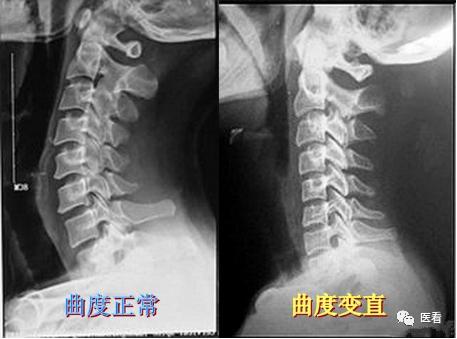

对比一下正常/曲度变直的X线:正常颈曲呈缓和、连续的生理前凸线,D点位于C4~C5前缘之间,D值:6mm~14mm(男), 5mm~13mm(女),其生物学意义在于增加其对抗纵向压力,维持颈椎的稳定。

测量弓顶位置:从齿状突尖至C7椎体后下缘划线,正常生理弓的弓顶应在C5椎体后上缘。如果弓顶不在C5椎体后上缘而在其下者为弓顶下移,或在C5椎体后上缘以上者为弓顶上移,均提示颈椎某节段有病变存在的可能。 C值:正常12mm±5mm

弓顶距离的测定:从齿状突向C7椎体后缘作一连线,弓顶的椎体后缘至连线之间的距离,为弓顶距离(即弧弦距),正常为12mm±5mm,小于7mm为生理弓平直,大于17mm为生理弓过度前屈。